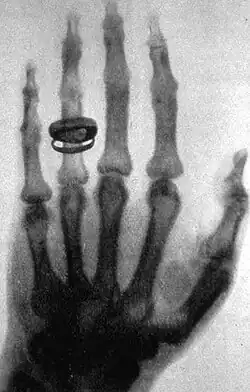

X-ray of a hand. X-rays are a common medical test.

A medical test is a medical procedure performed to detect, diagnose, or monitor diseases, disease processes, susceptibility, or to determine a course of treatment. Medical tests such as, physical and visual exams, diagnostic imaging, genetic testing, chemical and cellular analysis, relating to clinical chemistry and molecular diagnostics, are typically performed in a medical setting.